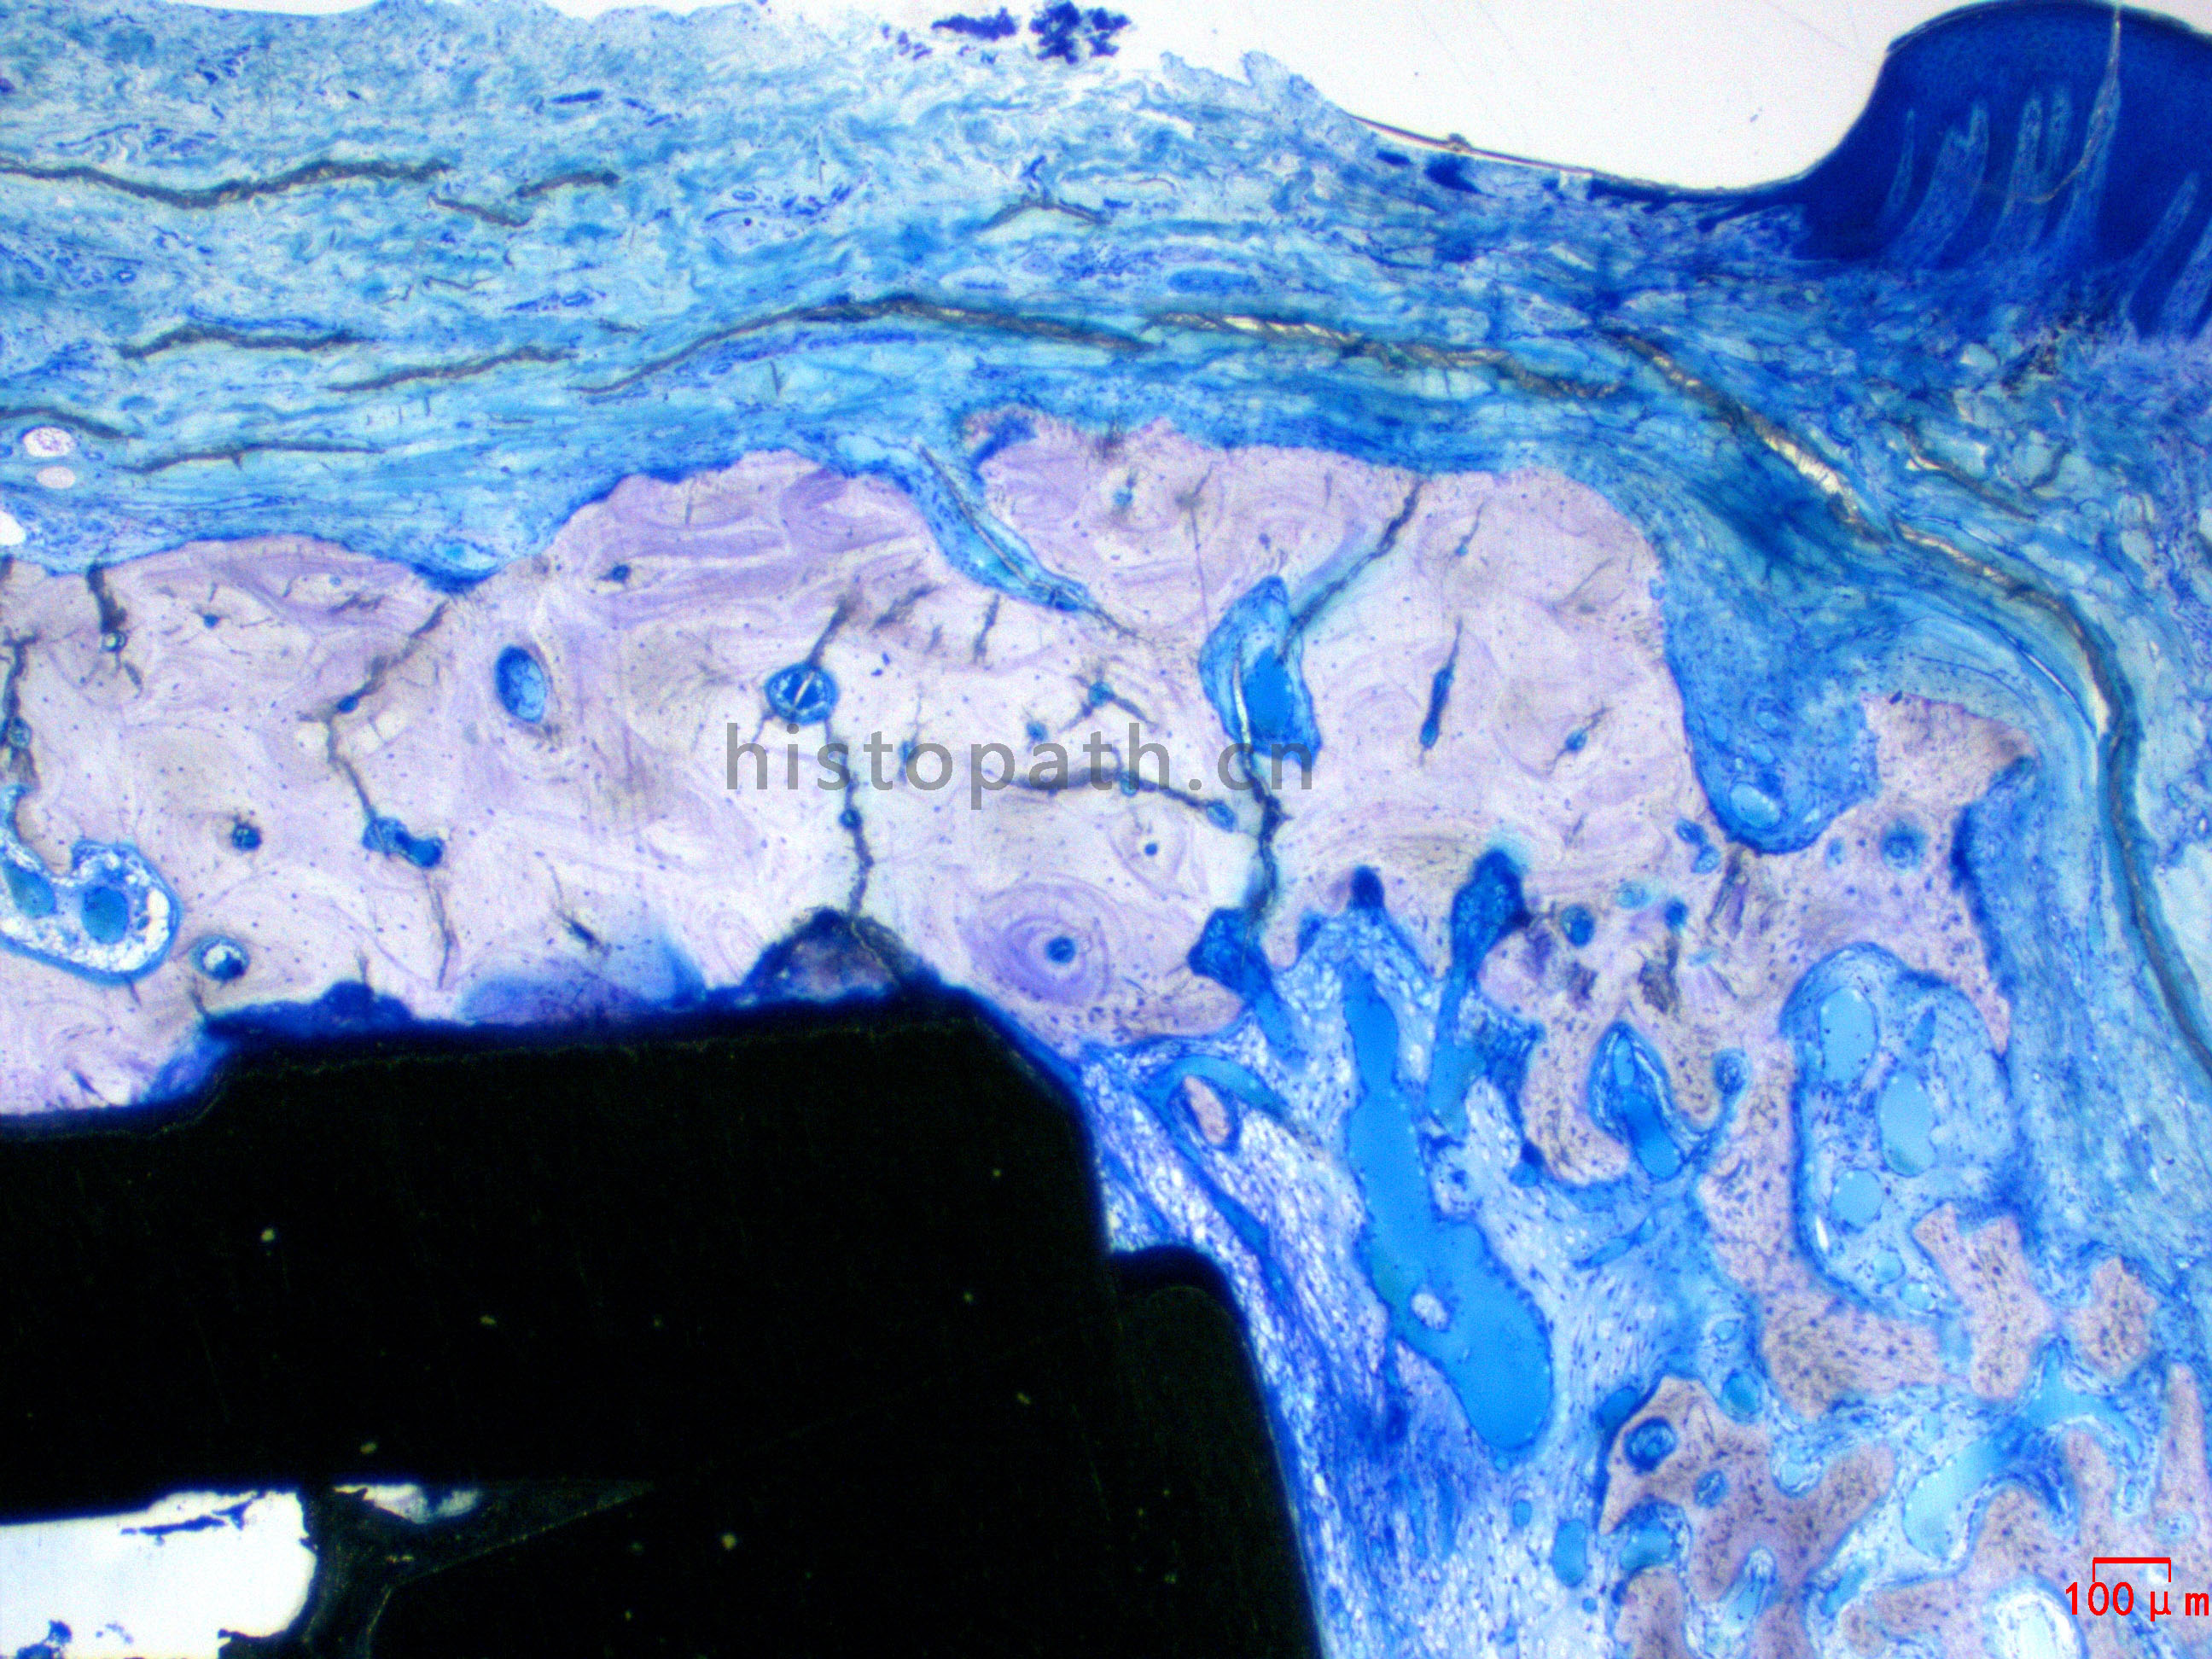

牙体种植:甲苯胺蓝染色

针对不同的病理阅片指标需求,行HE染色、Masson染色、亚甲基蓝-酸性品红染色、VG染色、Movat染色等。